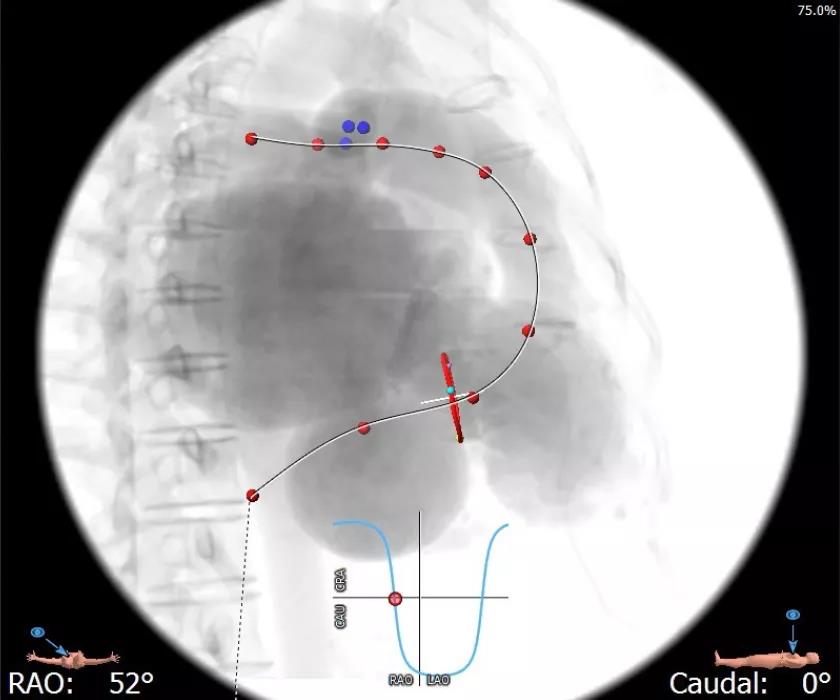

3. 由于患者存在一定程度的心脏解剖变异,右房扩大,右心室相对较小,右房与右室几乎平行,容易造成导丝跨瓣后顶住较薄的心室壁,在右室造成对心室壁的损伤甚至穿孔风险。所以,计划更换另一安全的解剖结构,使支撑导丝塑形后放入肺动脉支撑,既可得到稳定可靠的支撑,又极大减少心室穿孔风险,并且术前模拟释放途径也简单可行。

3.经股静脉入路送入16F E-sheath可扩张导管鞘,随后送入SAPIEN 3球扩瓣1输送系统,由于肺动脉入路朝上走,无需调弯,顺利跨瓣,将SAPIEN 3球扩瓣送入预定位置。精准定位后,以160次/分快速起搏,并保证1:1完全夺获,缓慢释放瓣膜。术后超声检查结果显示即刻跨瓣压差从术前9mmHg降至3mmHg,顺利完成瓣膜释放,回撤导管、导丝。